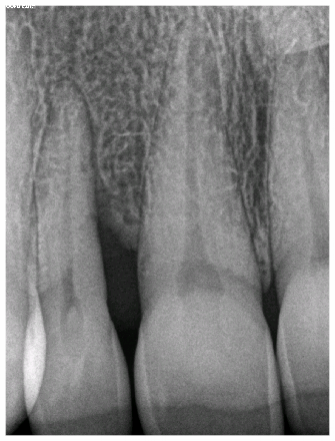

Before After

The before and after x-rays of the front tooth demonstrating a healthy bone refill. This is an exceptional result using non-surgical treatment. Perioscopy allowed us to both save this tooth from extraction and the smile of the patient.